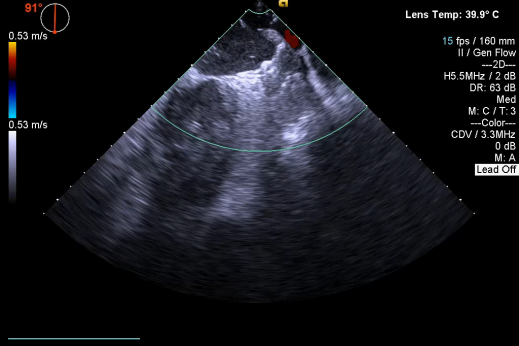

开释后,DSA与TEE观察均无残存分流

其中首场公开演示的左心耳血栓封堵病例拥有极高难度,患者术前TEE显示左心耳血栓形成伴机化,血栓位于心耳中段,近中端絮状物显著 。封堵机遇只有一次,选型和操作稍有失误,城市增长手术风险 。因而手术采取全麻,并装置了抗栓塞脑动脉;ぷ爸,以削减术中风险 。通过TEE疏导下丈量左心耳大幼以及确认左心耳血栓地位,李岳春教授凭借自身丰硕经验最终决定使用LAmbre 2632型号,选取推送式植入法将左心耳血栓牢牢锁死于远端,并且封堵器一次成型,封堵成效极佳,实现后取出脑;ぷ爸,均未见血栓,顺利实现了此台高难度的手术,获得了学员们的一致认可 。